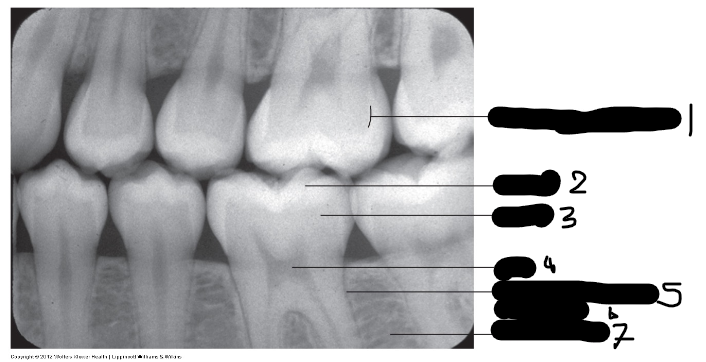

Glazuur-dentine grens, Dentinoenamel junction (Radiografisch)(Afbeelding)

1

Glazuur, Enamel (Radiografisch)(Afbeelding)

2

Dentine, Dentin (Radiografisch)

3

Pulpa, Pulp (Radiografisch)(Afbeelding)

4

Ligamentum parodontale, Periodontal ligament (Radiografisch)(Afbeelding)

5 (Donkere lijn)

Alveolair bot, Alveolar bone (Radiografisch)(Afbeelding)

6